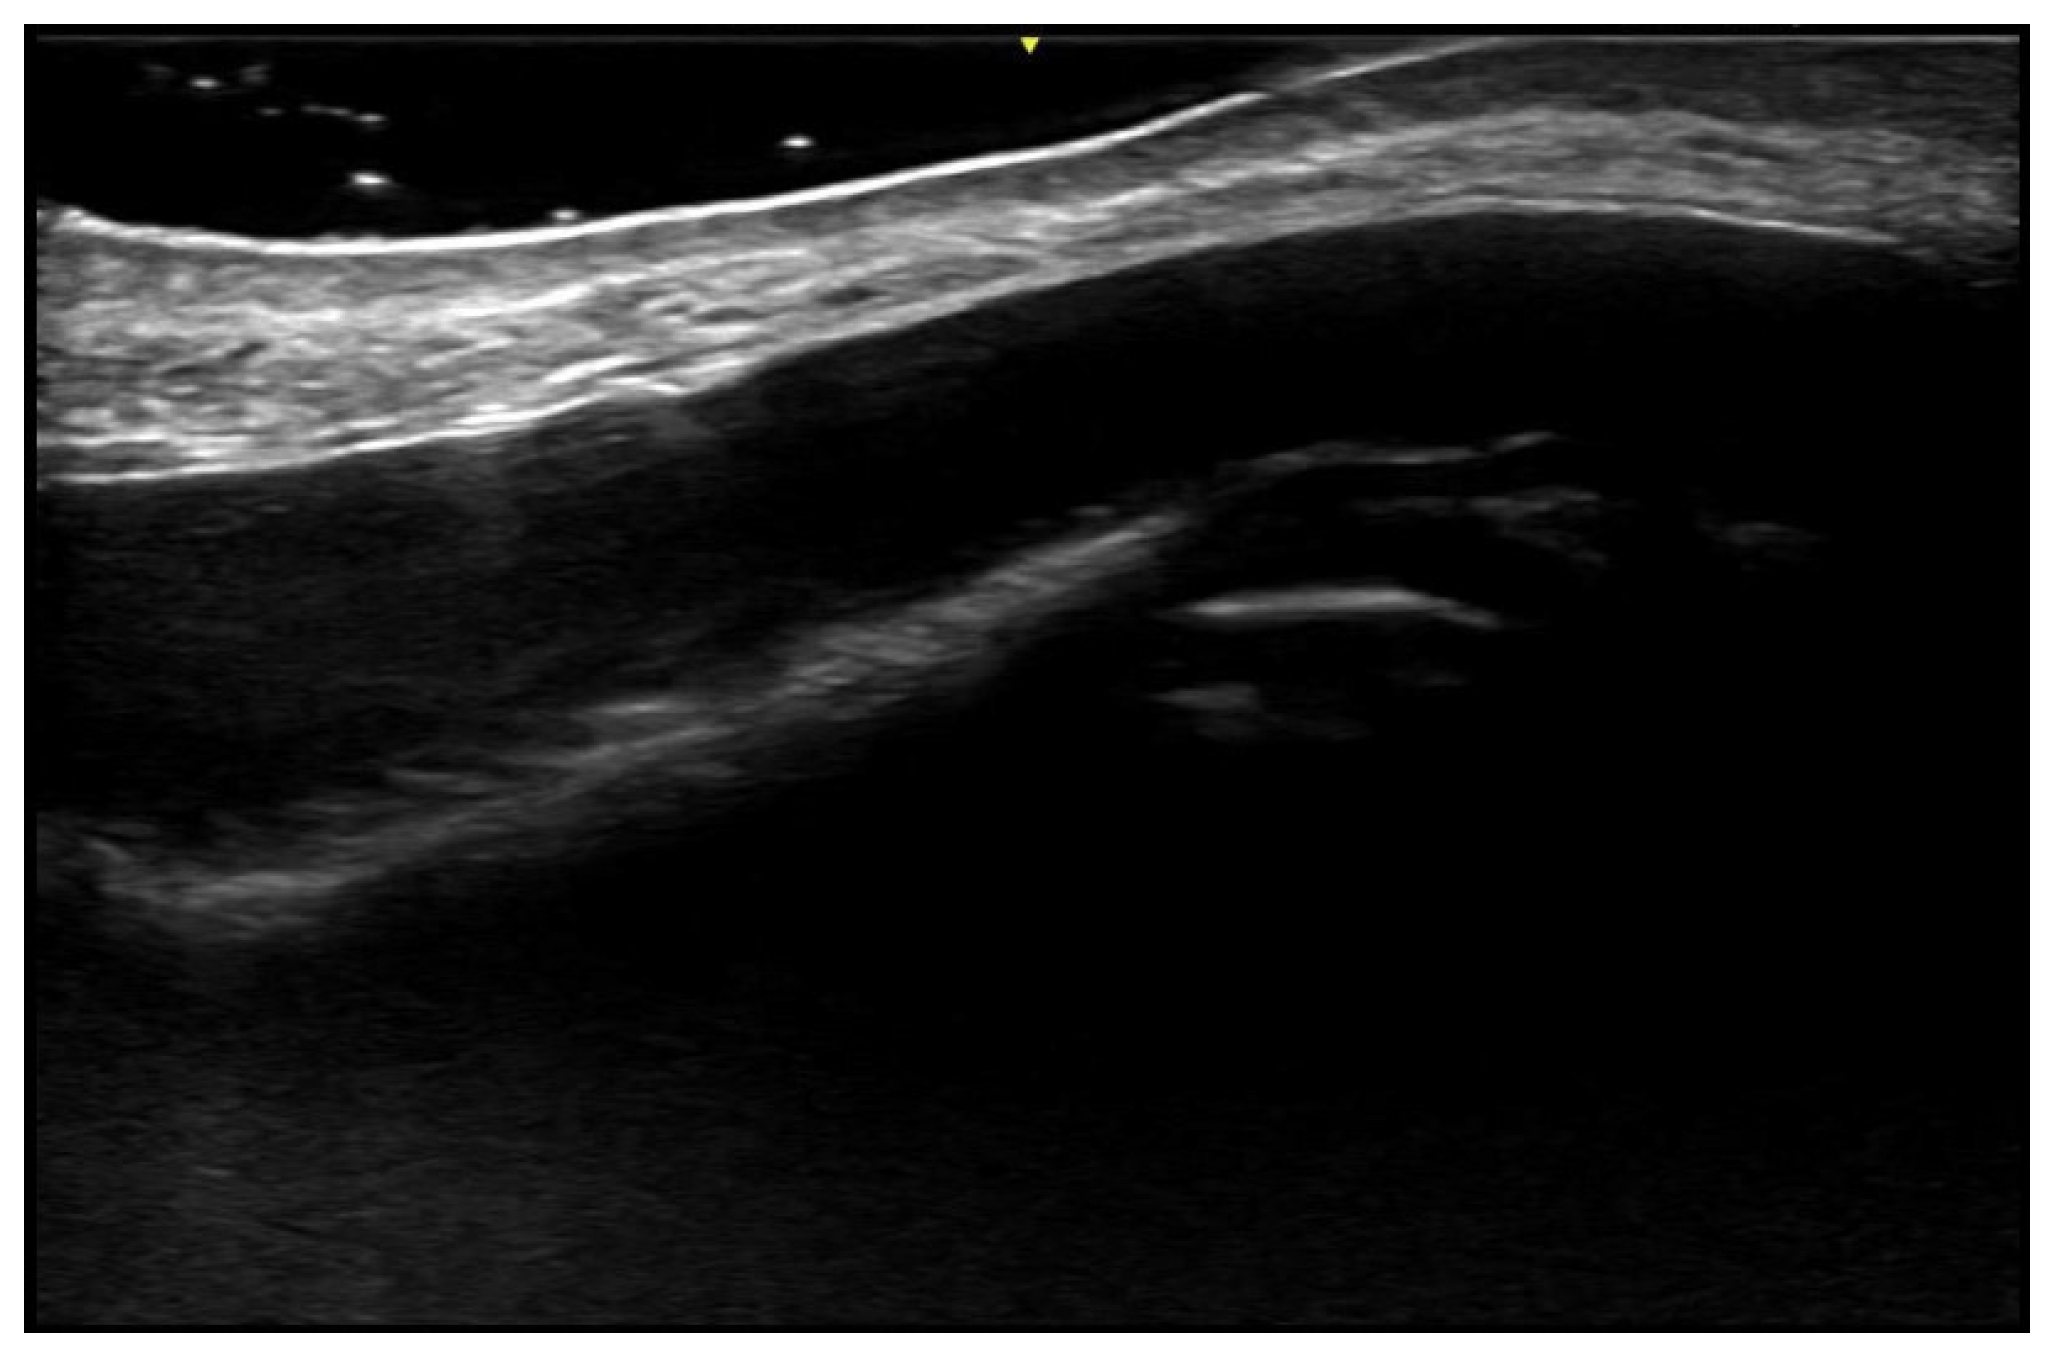

- Hayashi, A.; Giacalone, G.; Yamamoto, T.; Belva, F.; Visconti, G.; Hayashi, N.; Handa, M.; Yoshimatsu, H.; Salgarello, M. Ultra High-frequency Ultrasonographic Imaging with 70 MHz Scanner for Visualization of the Lymphatic Vessels. Plast. Reconstr. Surg. Glob. Open 2019, 7, e2086. [Google Scholar] [CrossRef] [PubMed]